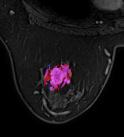

mri_logo

Breast MRI processing

Detecting breast cancer on MRIs using deep learning (MRI classification and segmentation)

Pytorch Segmentation Classification Deep learning Python Internship